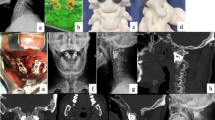

Illustrative case. A 50-year-old female presented with limbs weakness. (A) Preoperative sagittal CT showed BI-AAI with atlas occipitalization and congenital C2-3 fusion. (B) The latest-follow-up sagittal CT showed good reduction. (C) The latest-follow-up MRI showed the relieved foramen magnum stenosis. (D) Coronal CT showed good position of 3D-printed porous titanium cages. (E, F) parasagittal CT showed stable implants